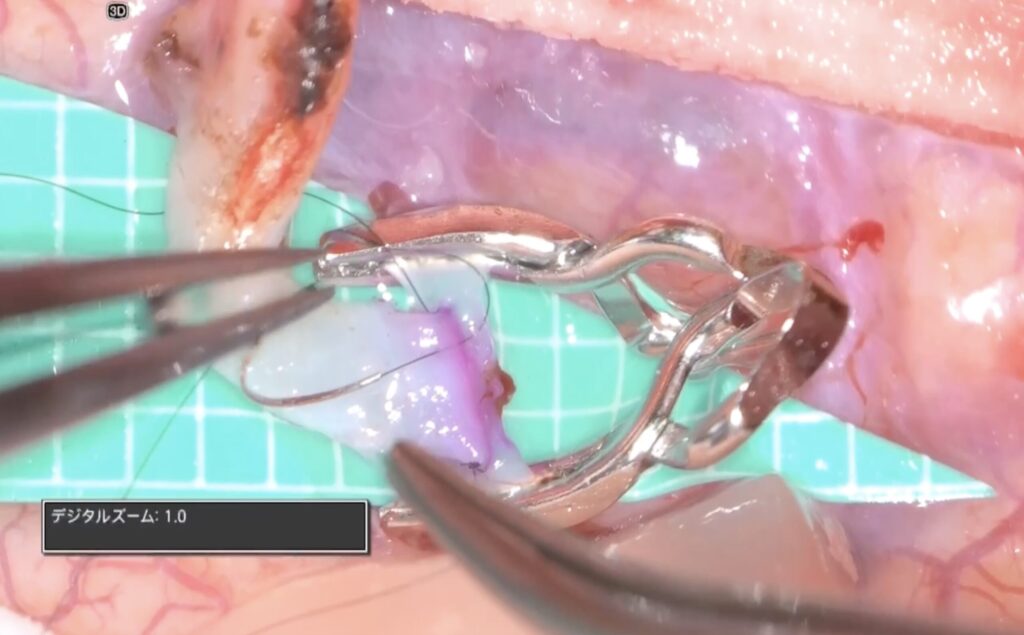

糸が通ったら、また瞬時にデジタルズームを切ります。

そして糸を結びます